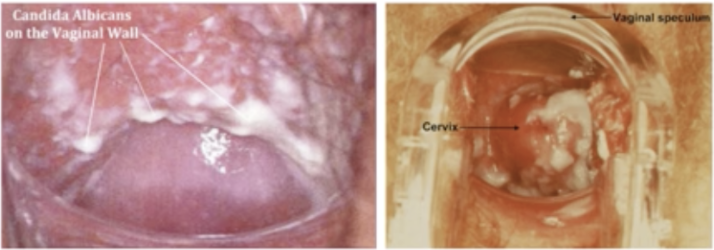

vulvovaginal candidiasis (VVC): uncomplicated vs complicated

overgrowth of Candida albicans or (other candida species) in the vagina, the vulva, the groin, and other moist areas and skin folds of the body

VVC physical exam findings

• thick, white, and curd-like vaginal discharge

• “cottage cheese discharge”

• Vulva erythematous; slight swelling

• vagina edematous and red

• most common: itchy vagina, burning and/or discharge

• dysuria, and dyspareunia

• pH < 4.5